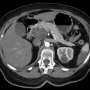

New reports from health experts reveal that the pancreas, a key organ responsible for producing hormones that regulate blood sugar and enzymes for digestion, can develop cancer, leading to severe health consequences. The latest data shows that pancreatic cancer is one of the most lethal forms of cancer, with a five-year survival rate of just 11%.

The symptoms to watch for include unexplained weight loss, jaundice (yellowing of the skin and eyes), and abdominal pain. These signs are often subtle and can easily be mistaken for other conditions. According to the Pancreatic Cancer Action Network, over 62,000 new cases are expected to be diagnosed in the United States in 2023, making it imperative for individuals to understand these warning signs.